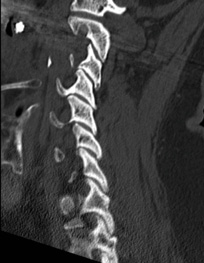

Pre-op MRI demonstrates partial disc height collapse and foraminal stenosis at C5-6 and C6-7.

Pre-op dynamic radiographs demonstrate partial loss of disc height at C5-6 and C6-7 without instability or scoliosis.

Pre-op CT demonstrates right C5-6 uncovertebral joint osteophyte causing foraminal stenosis but minimal facet arthrosis.